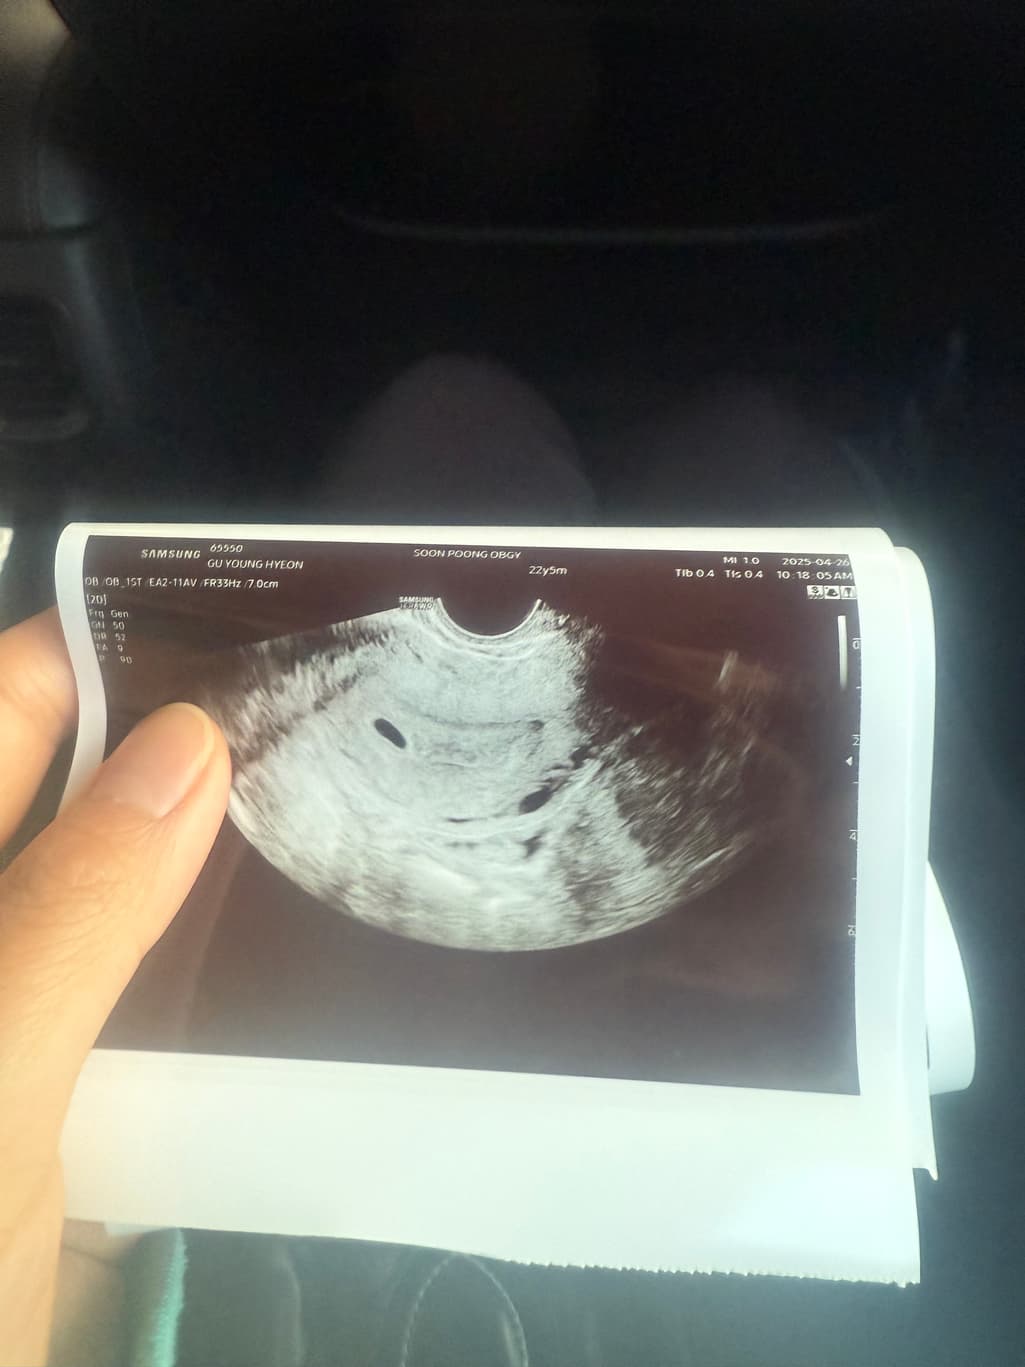

아기집 한개인거 맞죠???? 초음파 사진을 보니 동그란 구멍이 두개 있는것같아서요!!!!!!!!!!!!!!!!!’

한개 맞겠죠?

하나가 보이긴 하는데 그 아래 구조물 관련 자세한 초음파 해석은 담당 산부인과 전문의와 하시는게 가장 정확하고 안전합니다

담당의가 아기집이 한개라고 했으면 단태아가 맞을 것이고 의문이 남는다면 다음 방문에서 상의 해 보시기 바랍니다